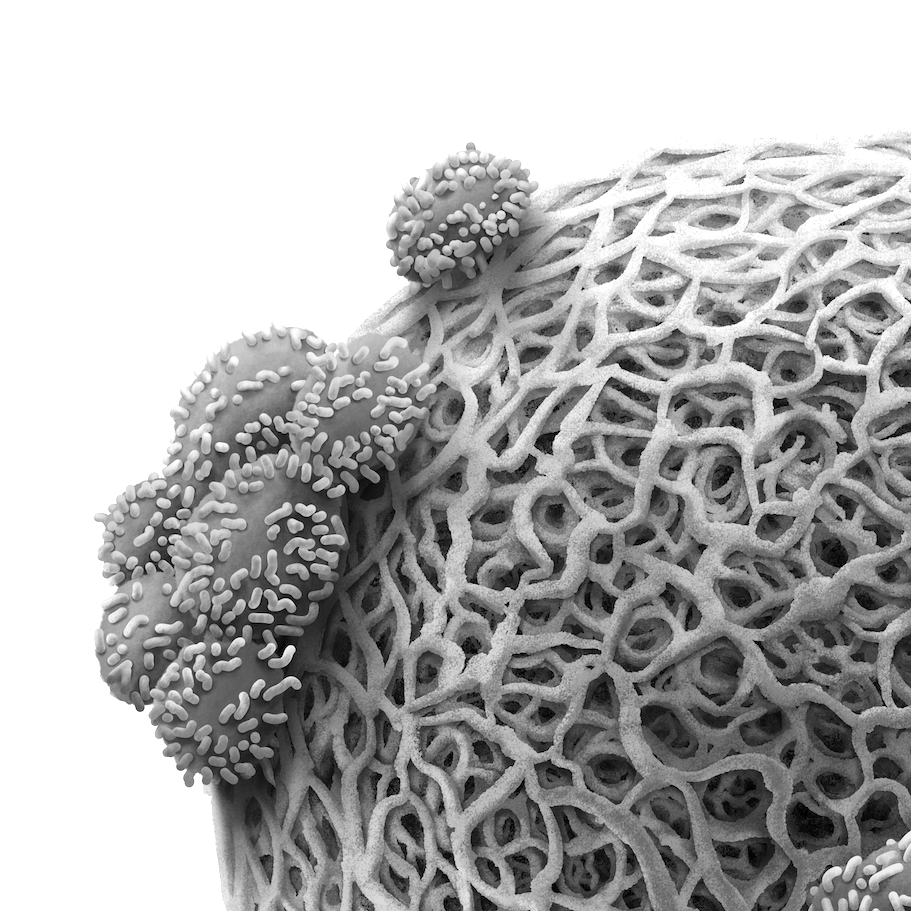

With an M.B.B.S. and M.D. in Anatomy, Dr Daron brings medical knowledge and precision to every project. By understanding the language of medicine, collaborations are seamless, ensuring your ideas are translated accurately.

Having taught anatomy for over four years, Dr Daron’s experience ensures that every illustration meets educational standards and communicates effectively to both students and professionals.

Trained through extensive, full-body human cadaver dissection—from head to toe—Dr Daron possesses a rare, in-depth understanding of human anatomy. This foundational experience allows for the creation of highly realistic, anatomically precise medical illustrations, setting a high standard for accuracy and detail in the field